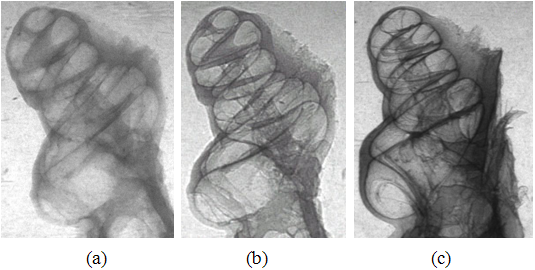

图6. 同步辐射多种成像方法比较,(a) 豚鼠耳蜗吸收衬度成像,(b) 豚鼠耳蜗同轴相位衬度成像,(c) 豚鼠耳蜗衍射增强相位衬度成像。豚鼠耳蜗对声音非常灵敏,豚鼠耳蜗与人耳蜗相似,是耳科专家研究听力的好材料。豚鼠耳蜗样品由首都医科大学提供。

图7 鱼成像比较,(a) 吸收衬度成像,(b) 衍射增强相位衬度成像。从两幅图像的比较,可以显示相位衬度成像可以获得比吸收衬度成像高得多的衬度。